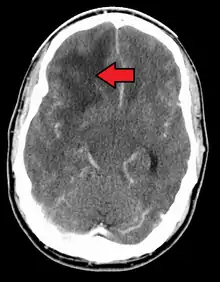

When viewed with MRI, glioblastomas often appear as ring-enhancing lesions. The appearance is not specific, however, as other lesions such as abscess, metastasis, tumefactive multiple sclerosis, and other entities may have a similar appearance.[56] Definitive diagnosis of a suspected GBM on CT or MRI requires a stereotactic biopsy or a craniotomy with tumor resection and pathologic confirmation. Because the tumor grade is based upon the most malignant portion of the tumor, biopsy or subtotal tumor resection can result in undergrading of the lesion. Imaging of tumor blood flow using perfusion MRI and measuring tumor metabolite concentration with MR spectroscopy may add diagnostic value to standard MRI in select cases by showing increased relative cerebral blood volume and increased choline peak, respectively, but pathology remains the gold standard for diagnosis and molecular characterization.